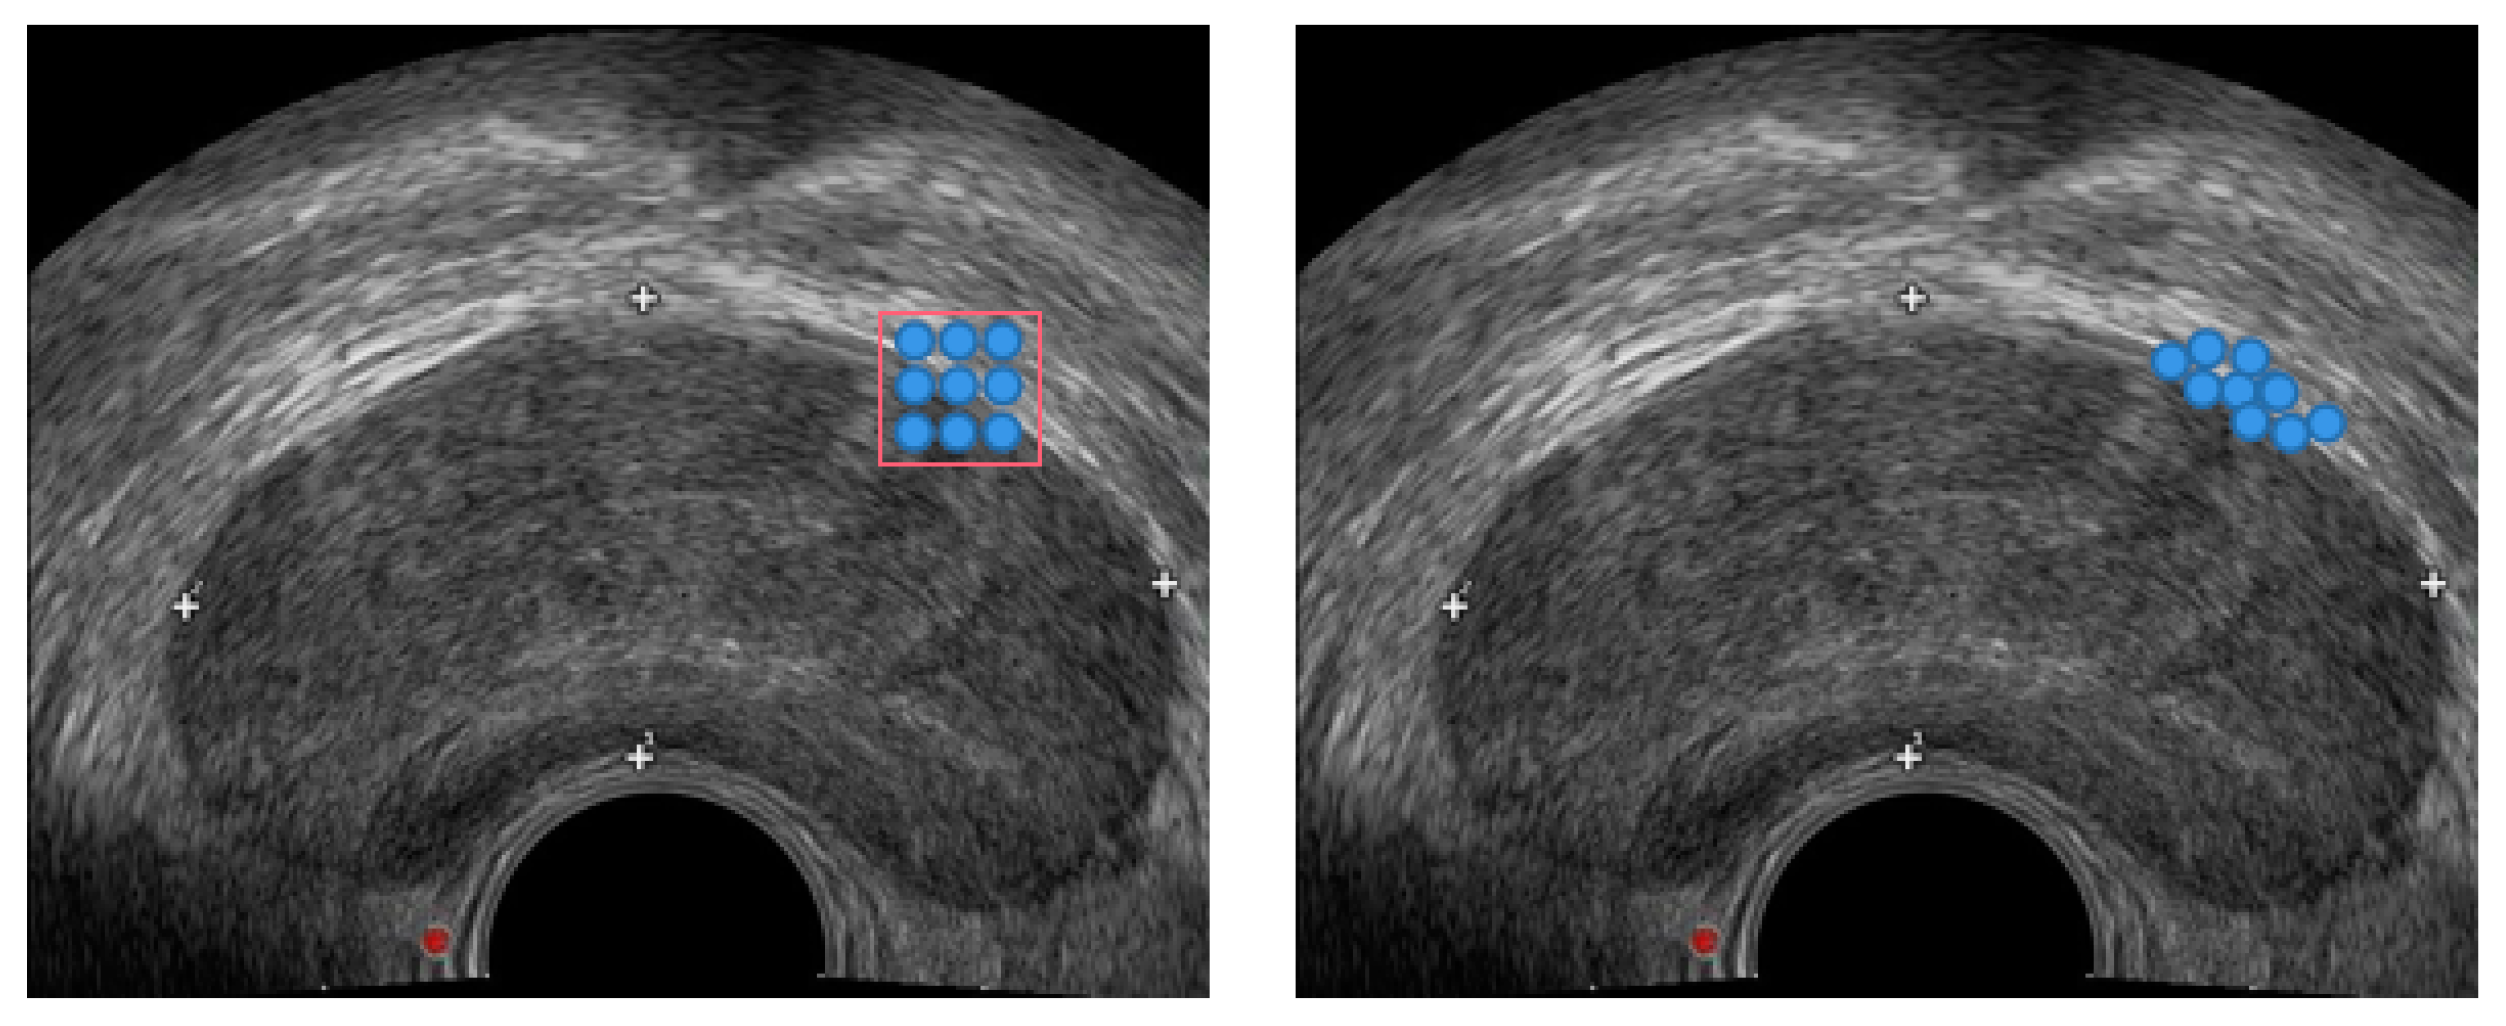

2.1. Data Preprocessing

3.1. Dataset